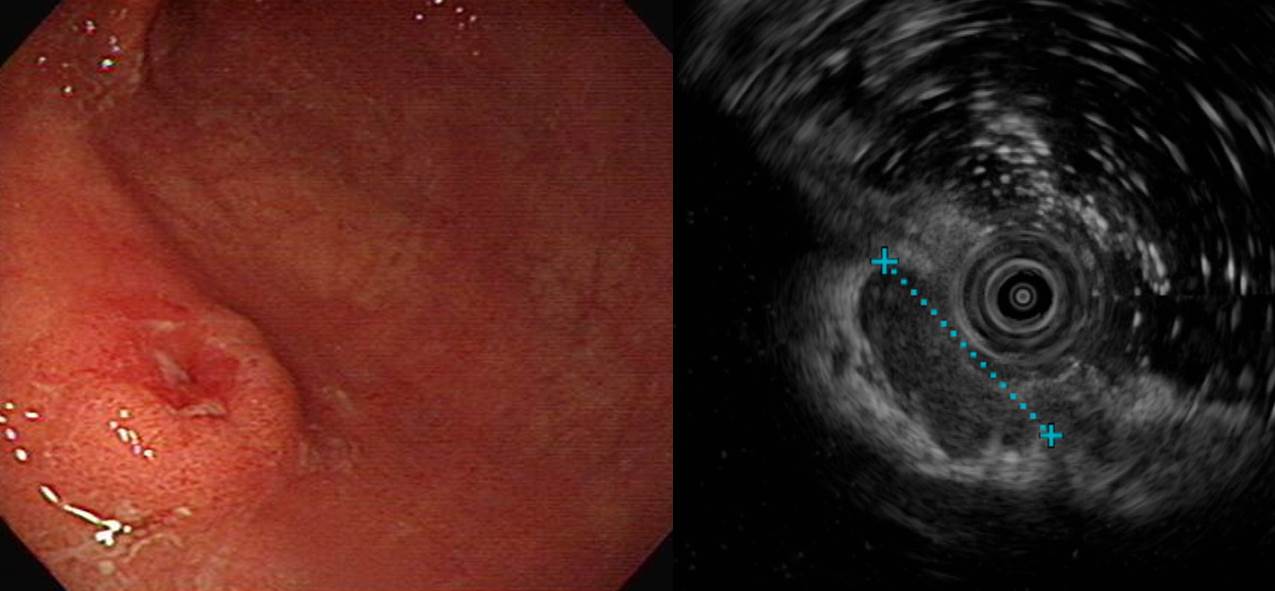

Depth of invasionÀº SM3¿´½À´Ï´Ù.

1. Location : upper third, center at cardia (Siewert III)

2. Gross type : Borrmann type 2

3. Histologic type : Medullary carcinoma (lymphoepithelioma-like carcinoma)

4. Histologic type by Lauren : indeterminate

5. Size : 2.2x2.2 cm

6. Depth of invasion : invades muscularis propria

7. Resection margin: free from carcinoma, safety margin: proximal 1.4 cm, distal 2 cm

8. Lymph node metastasis : no metastasis in 52 regional lymph nodes

9. Lymphatic invasion : not identified

10. Venous invasion : not identified

11. Perineural invasion : not identified

12. Result of in-situ hybridization: Epstein-Barr virus: Positive

Á¶Á÷°Ë»ç¿¡¼­´Â poorly differentiated adenocarcinoma¿´°í EUS¿¡¼­ SM invasionÀÌ ¶Ñ·ÇÇß½À´Ï´Ù.